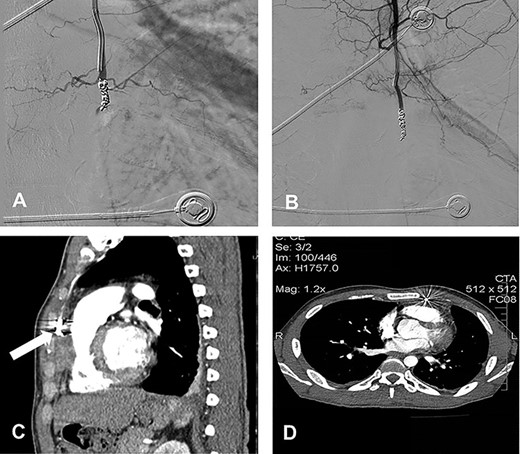

A 22-year-old man was admitted to our emergency department suffering of blunt thoracic trauma due to traffic accident. Clinical examination and performed radiological studies revealed fractures of multiple left-sided ribs, the sternum as well the Th11 and Th12 vertebral bodies. The patient was initially treated conservatively, but on the fifth day, he developed a left-sided pleural effusion, necessitating a thoracostomy tube. Additionally, there were subpectoral chest wall abscesses, which were surgically incised and drained. Blood as well pus cultures from the abscess cavities revealed the growth of Staphylococcus aureus; therefore, intravenous antistaphylococcal antibiotics were administered. However, in the further course, a control contrast-enhanced computed tomography (CT) scan demonstrated a big left IMA pseudoaneurysm (Fig. 1: white arrow) accompanied by an ipsilateral localized hemothorax (Fig. 1A–C). The effusion was drained again, and concerning the aneurysm, we preferred a minimally invasive treatment via coil embolization in order to avoid a potential extensive mobilization of the patient, contraindicated by his spinal injuries, while the positioning on the operating table in case of a surgical treatment through a lateral thoracotomy.

Contrast-enhanced CT with LIMA pseudoaneurysm (white arrow). (A) Sagittal plane; (B) coronal plane; (C) transverse plane with LIMA pseudoaneurysm (white arrow) and bilateral pleural effusions; (D) selective LIMA angiography demonstrating the aneurysm.